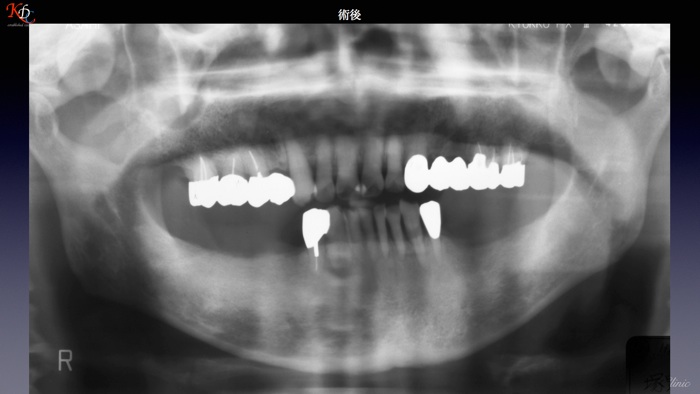

治 療例 1